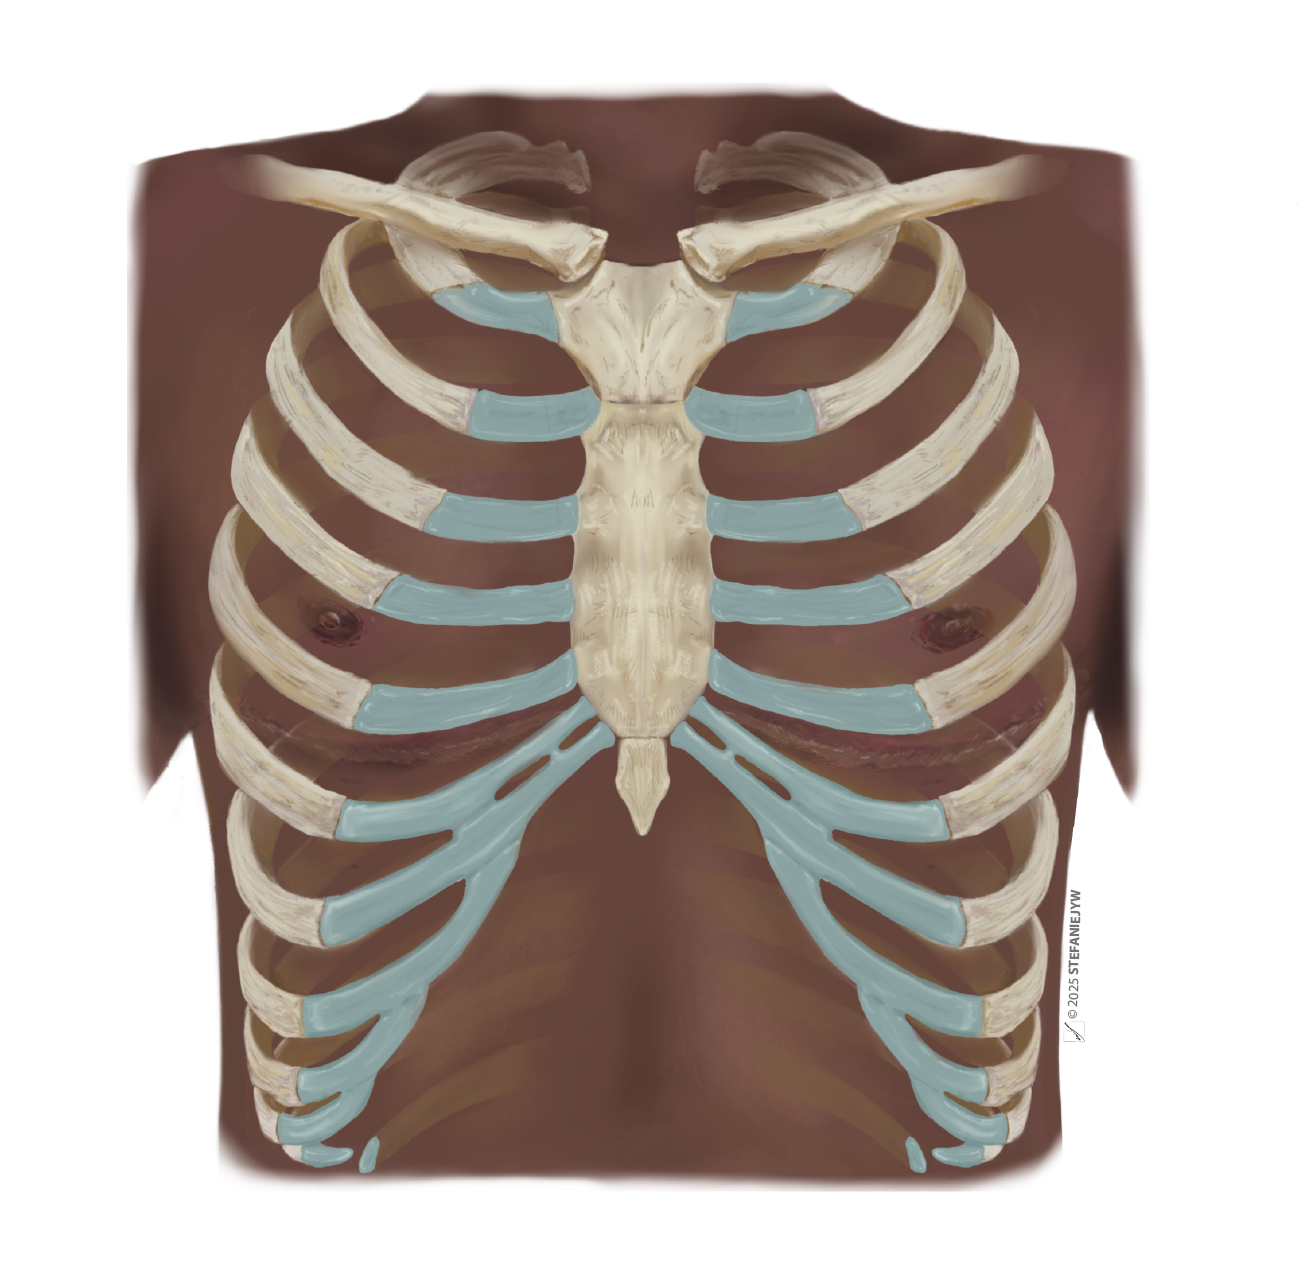

Series: Inclusive Anatomy